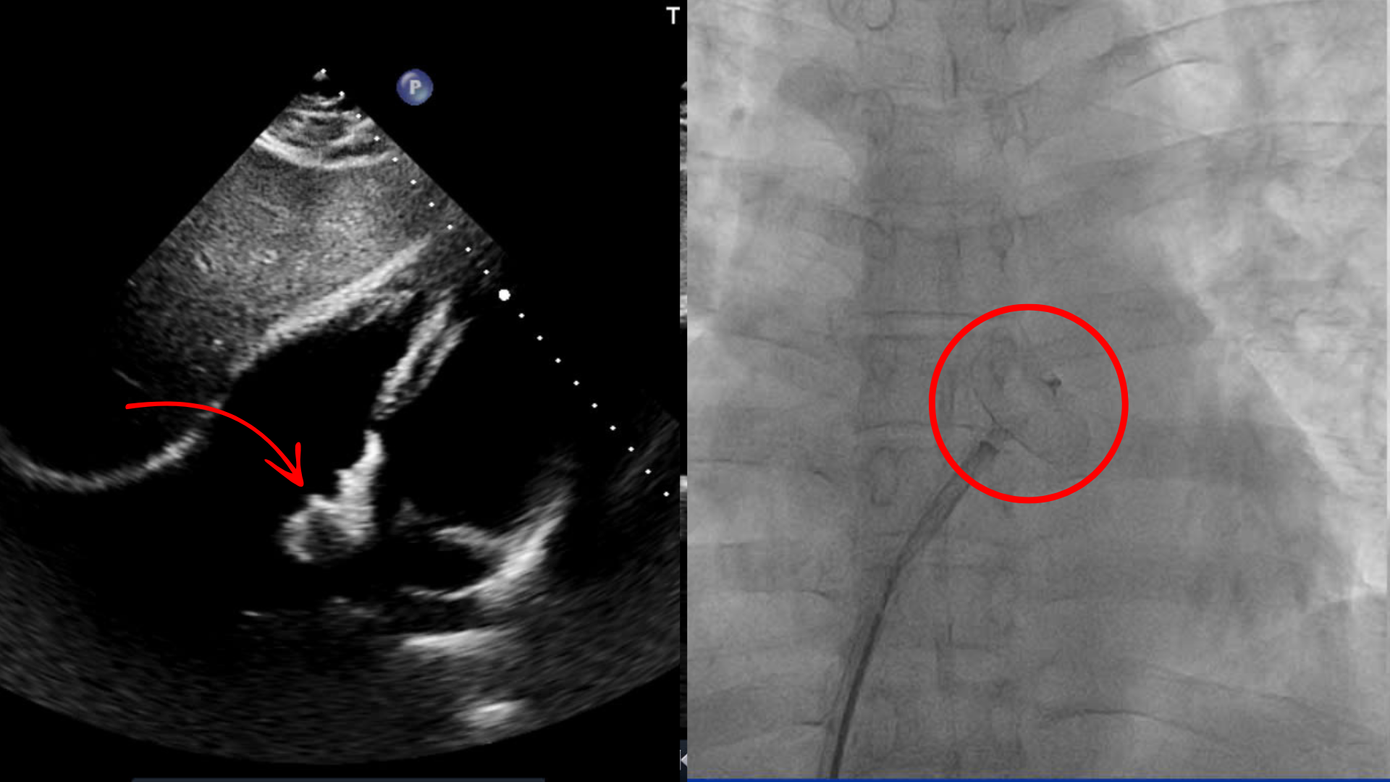

Sau khi thăm khám và thực hiện các xét nghiệm, điện tim, siêu âm tim kỹ càng, các bác sĩ phát hiện anh Lâm bị thông liên nhĩ lỗ thứ 2, đường kính 10x16mm. Đây là một dị tật tim bẩm sinh thường gặp, chiếm khoảng 10% trong các bệnh tim bẩm sinh ở người lớn với sự xuất hiện của một lỗ thủng giữa hai buồng tâm nhĩ.

“Bệnh nhân Lâm được chẩn đoán bệnh kịp thời ở giai đoạn sớm với các triệu chứng cảnh báo ban đầu, vì vậy có thể áp dụng phương pháp điều trị an toàn, ít xâm lấn. Ê kíp bác sĩ đã khảo sát kỹ hình thái, cấu trúc, chức năng tim, với gờ chủ bám tốt của bệnh nhân Lâm rất phù hợp để điều trị bằng phương pháp đóng lỗ thông liên nhĩ bằng dù qua da dưới hướng dẫn của hệ thống siêu âm tim”. Bác sĩ Hải chia sẻ.

Trong quá trình đóng lỗ thông liên nhĩ bằng dù có kích thước 24mm cho anh Lâm, bác sĩ đã tiến hành tiếp cận vào đường tĩnh mạch đùi phải, đem dụng cụ theo đường dẫn mạch máu lên tim, khéo léo thả từng cánh dù để đóng kín lỗ thông liên nhĩ.

Kết quả siêu âm sau can thiệp cho thấy dụng cụ bít thông liên nhĩ nằm đúng vị trí trên vách liên nhĩ, lỗ thông đã được bịt kín hoàn toàn, chức năng tâm thu thất trái bình thường, áp lực động mạch phổi không tăng. Sau 02 ngày anh Lâm xuất viện, trở về cuộc sống sinh hoạt bình thường.

| Lỗ thông liên nhĩ đã được bít dù của bệnh nhân Lâm |